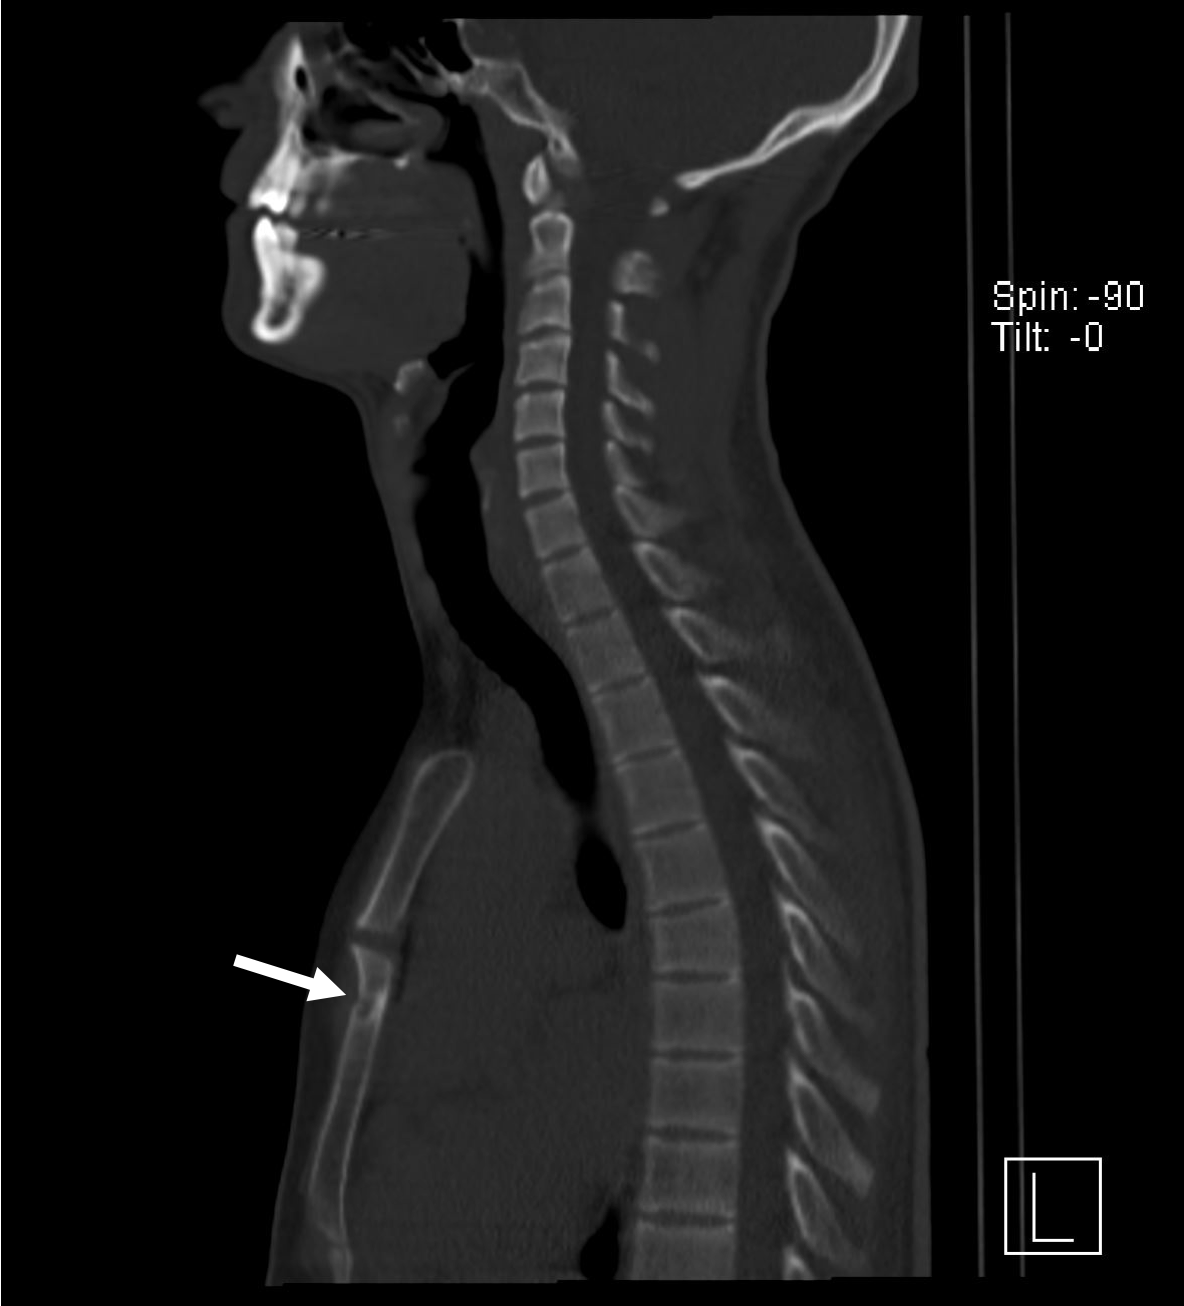

An ultrasound examination of the chest performed using a Toshiba Aplio 500 high-frequency probe showed an acute linear fracture through the anterior cortex of the sternum just below the level of the sternomanubrial joint (FIGURE 1). The subjacent third costal cartilage was unremarkable. A bone densitometry DEXA scan showed osteoporosis of the L2-L4 vertebral bodies with both T-score and Z-scores measuring -2.9 (FIGURE 2). Bone density of the bilateral femora was normal (T score -0.9). Further imaging of the neck was arranged to investigate the cause of the inappropriate parathyroid hormone levels. An ultrasound of the neck revealed a well-defined, hypoechoic nodule located just inferior to the lower pole of the left lobe of the thyroid gland measuring 14x8x5mm (FIGURE 3). The patient then underwent a SPECT-CT of the neck and chest to ensure co-localisation on two imaging modalities. 739 MBq of technetium 99m was injected and acquisitions were obtained at 10min, 90mins and 180mins following tracer injection. Analysis of the SPECT data demonstrated a well-defined area of retained activity situated in the lower pole of the left lobe of the thyroid which correlated well with the findings of the ultrasound scan (FIGURE 4). The overall appearances were in keeping with a parathyroid adenoma situated in the lower pole of the left lobe of the thyroid. The CT component of the study also showed a further view of the fracture (FIGURE 5).